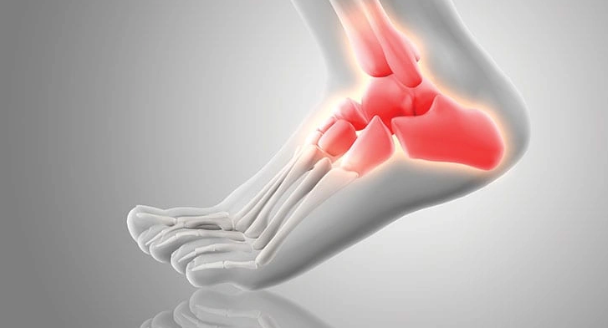

발목 통증?

발목 통증은 발목관절에 느껴지는 불편감이나 통증을 말합니다. 경증부터 중증까지 다양하며 갑자기 발생하거나 시간이 지남에 따라 점진적으로 발생할 수 있습니다. 발목 통증은 한쪽 또는 양쪽 발목에 영향을 미칠 수 있으며 다양한 요인에 의해 발생할 수 있습니다.